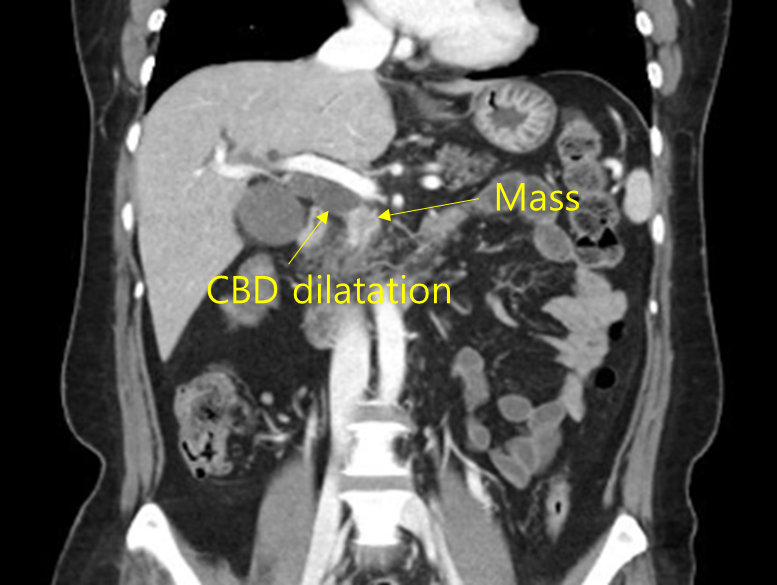

48세 여자가 2주 전부터 소화가 잘 되지 않고 1주 전부터 황달 및 가려움증이 있어서 병원에 왔다. 2주 동안 몸무게도 3 kg 정도 줄었다고 한다. 평소 건강하였다고 한다. 혈압 130/80 mmHg, 맥박 77회/분, 호흡 18회/분, 체온 37.6℃이다. 공막에 황달이 있으며, 배 청진에서 장음은 정상이고 오른쪽 윗배에서 압통이 없는 계란 크기의 덩이가 만져진다. 혈액검사 결과는 다음과 같다. 복부 컴퓨터단층촬영 사진과 자기공명담췌관조영술 사진이다. 치료는?

백혈구 4,200/mm3, 혈색소 11.4 g/dL, 혈소판 202,000/mm3, 아스파르테이트아미노전달효소 78 U/L, 알라닌아미노전달효소 66 U/L, 총빌리루빈 13.66 mg/dL, 알칼리인산분해효소 365 U/L, 암항원(CA) 19-9 372.5 U/mL (참고치, <37), 암배아항원(CEA) 2.17 ng/mL (참고치, <5)

Img | CT: Periampullary mass, proximal CBD dilatation MRCP: Distal CBD narrowing, proximal CBD dilatation |

Imp: 원위부 담관암(distal cholangiocarcinoma)

DDx: 이자머리암(pancreatic head cancer) 등 기타 periampullary cancer

임상양상, 혈액검사, 영상검사상 모두 원위부 담관암이 의심되므로 pancreaticoduodenectomy를 시행한다.

• 이는 CT와 MRCP에 각각 mass와 proximal CBD dilatation이 보이는 것으로 다시 확인할 수 있다.